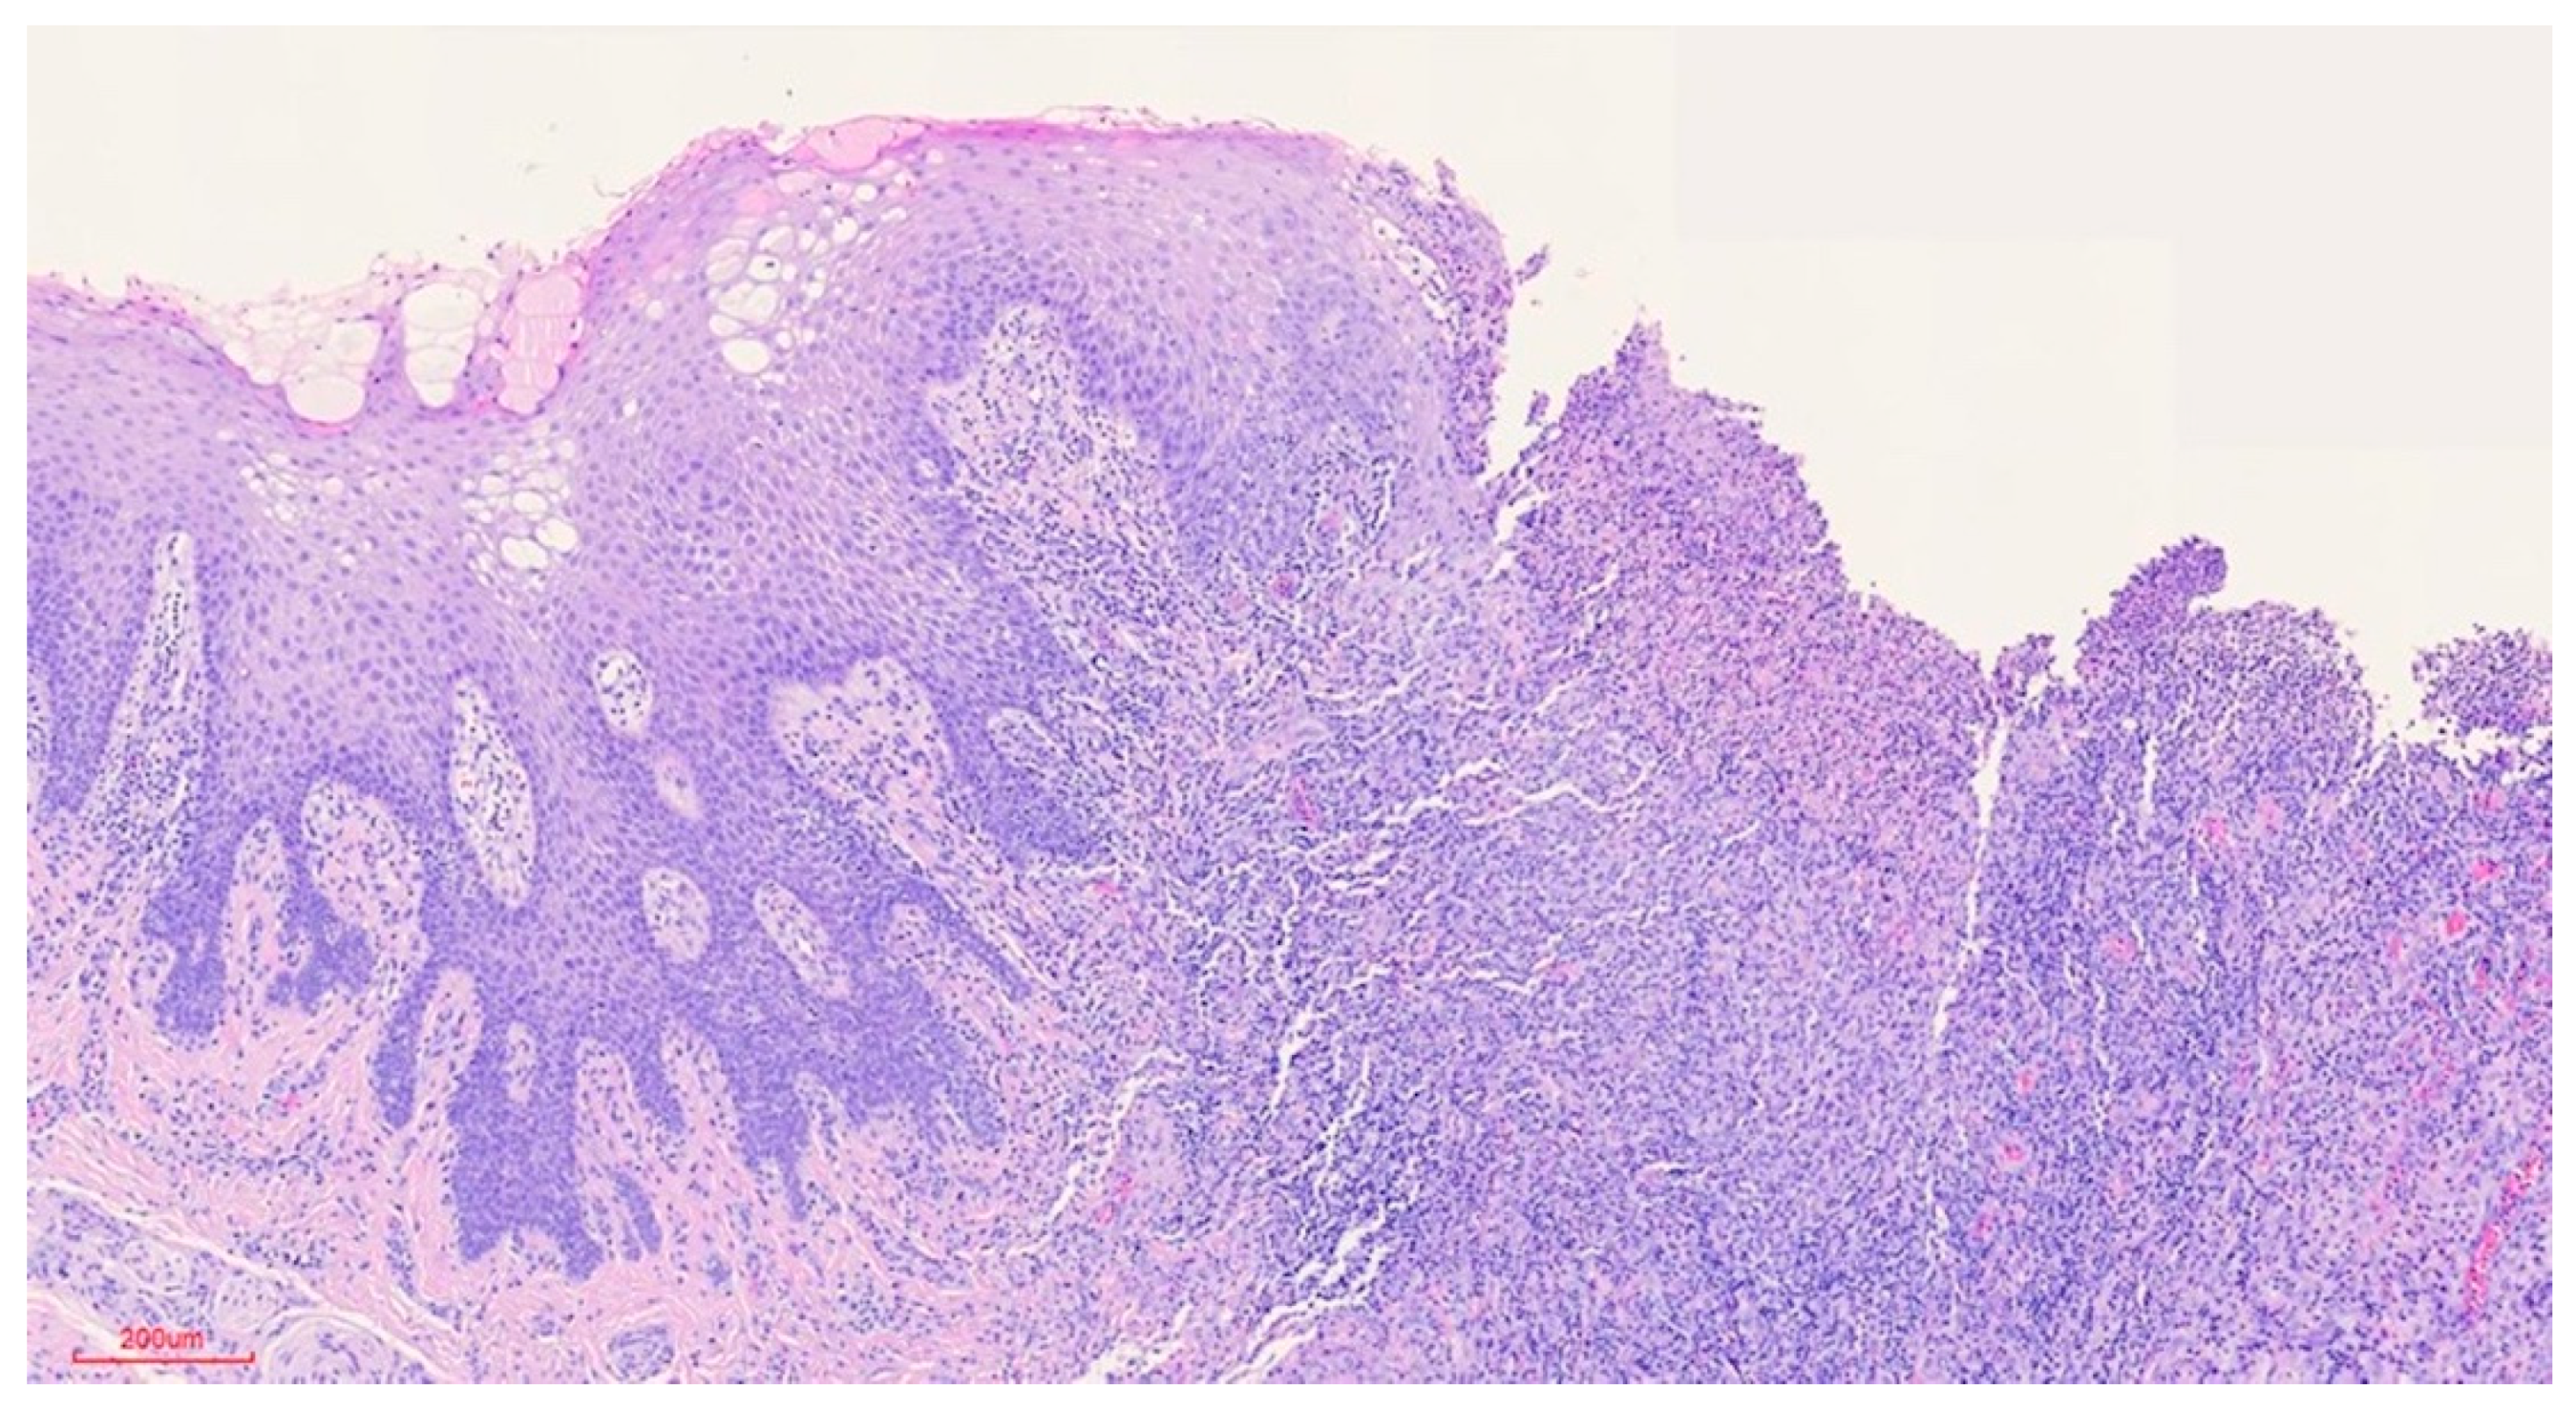

Clinically, the lesion usually has a raised hyperkeratotic border and microscopically it is characterised by a dense infiltrate of T and B lymphocytes, macrophages and mainly eosinophils24 and a tendency to penetrate the underlying muscle.

b) Microscopic findings: infiltrative ulcerative lesion covered with necrotic-fibrinoid material and consisting of an abundant polymorphous inflammatory infiltrate extending in depth around the seromucinous glands and dissociating the muscle fibres. It consists of cells of histiocytic type, lymphocytes, polynuclear neutrophils and abundant eosinophils. PAS and Grocott stains show no fungal elements. No signs of malignancy are observed (see Figures 4–9).

Figure 4.

Preprints 77661 g004

Figure 5.

Preprints 77661 g005

Figure 6.

Preprints 77661 g006

Figure 7.

Preprints 77661 g007

c) Histopathological diagnosis: histological aspect compatible with traumatic ulcerative granuloma with stromal eosinophilia.